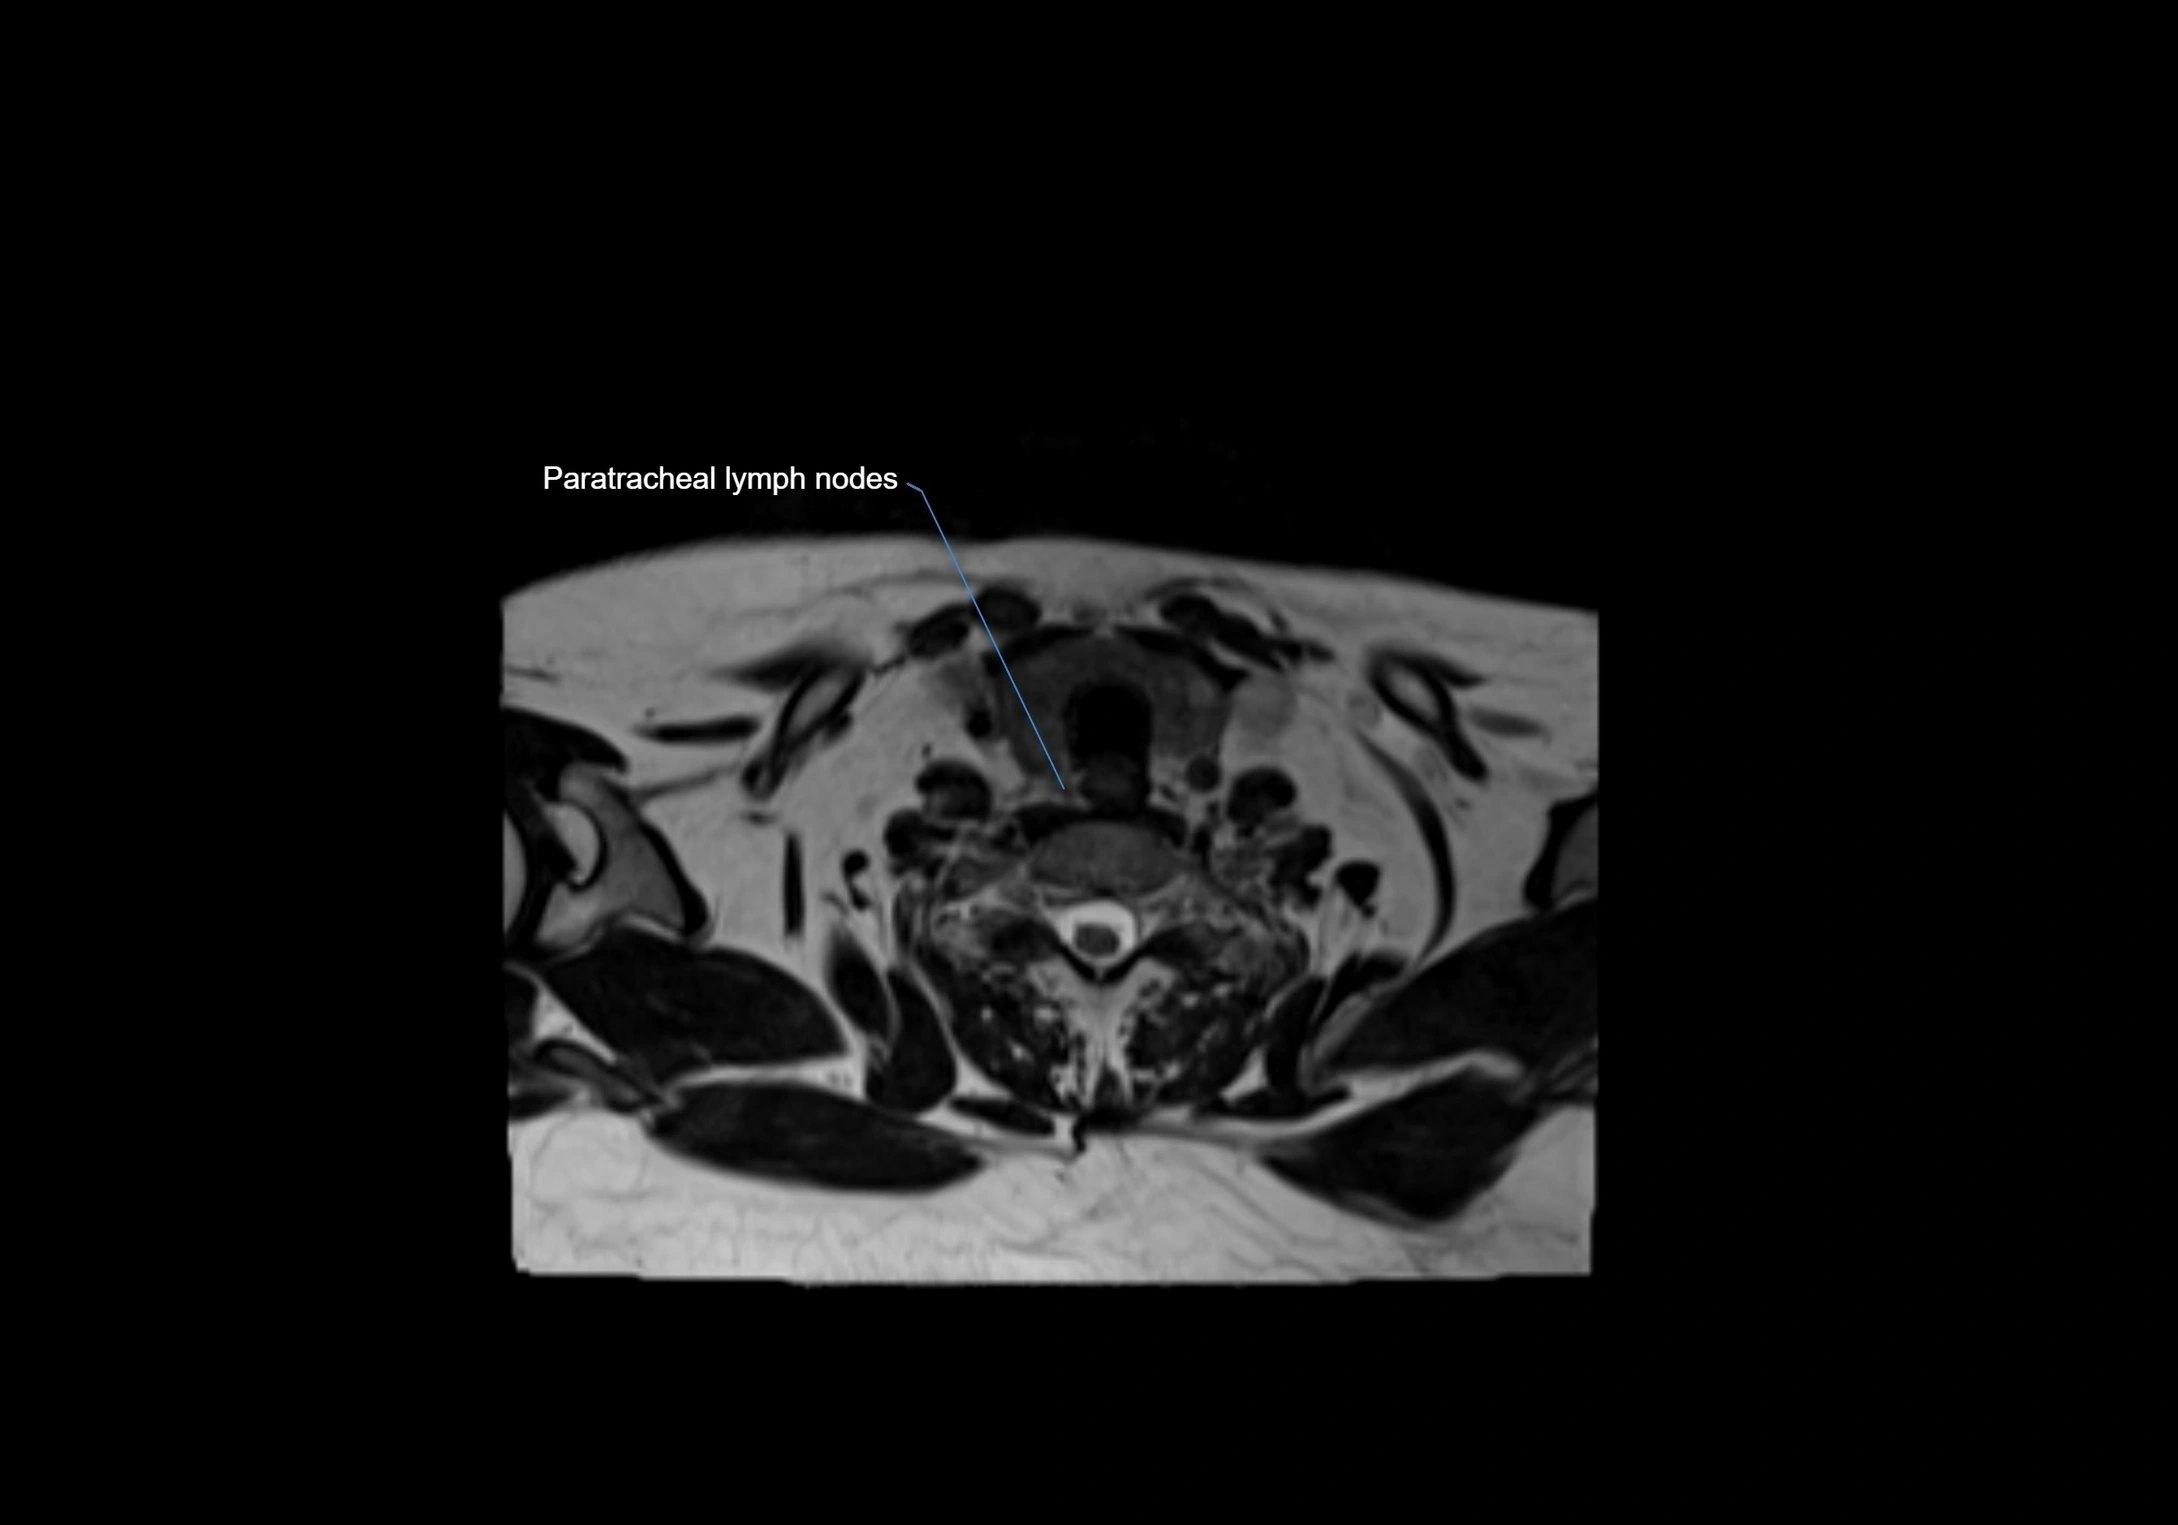

Location

• Found along primary lymph node chains, including preauricular, submandibular, parotid, and occipital regions

MRI Appearance

T1-weighted images:

• Normal accessory nodes appear as small, oval hypointense to intermediate signal structures within subcutaneous fat

• Surrounded by hyperintense fat, enhancing contrast for visualization

• Pathological nodes may appear enlarged or rounded, sometimes with cortical thickening

MRI images

image